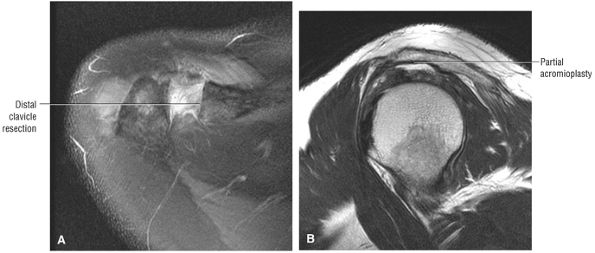

FIGURE 8.102 ● (A) The anterior undersurface of the acromion and the coracoacromial ligament form the coracoacromial arch. The subacromial subdeltoid bursa facilitates the passage of the rotator cuff and proximal humerus under the coracoacromial arch. (B) A superior axial image shows the anterior-to-posterior extent of the coracoacromial (CA) ligament perpendicular to the supraspinatus tendon. The fluid in the subacromial-subdeltoid bursa represents fluid between two serosal surfaces in contact with each other. One serosal surface is contributed by the undersurface of the coracoacromial arch and deltoid, and the other serosal surface is on the bursal side of the cuff.

|

![]() |